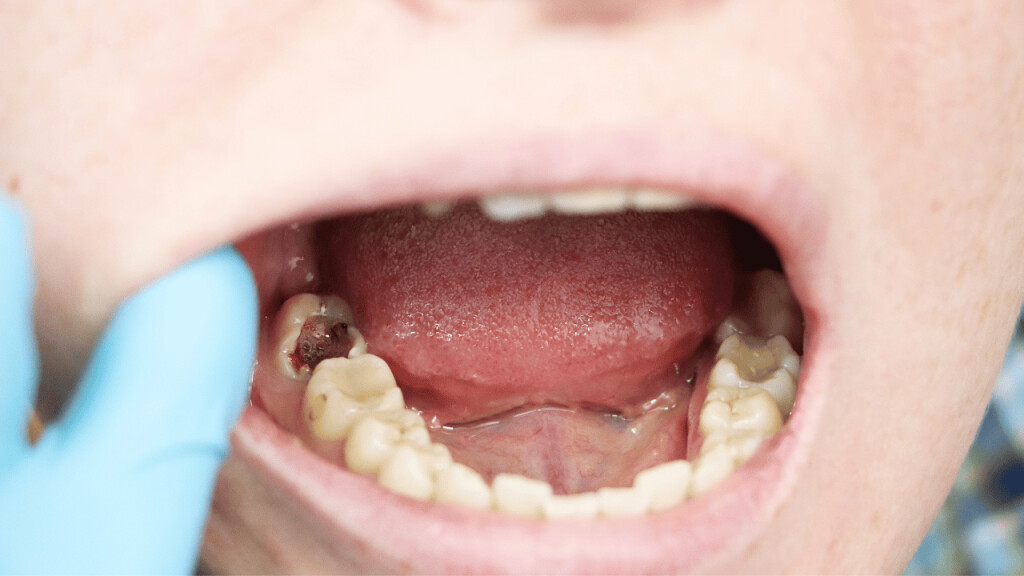

A loose tooth can be very annoying and discomforting. Your oral hygiene, gum disease, teeth grinding, hard food, mouth injury, anything can result in a loose tooth. You can let your tooth come out on its own. But the issues that come with that, like problems in eating food, constant sensitivity, etc can be hard to bear. And you just can’t keep waiting for your tooth to fall on its own for a long time. So, how to get a tooth out in a fast and painless way?

How to pull an adult tooth out without pain?

There are a few ways through which you can pull out a loose tooth without hurting yourself. However, if you are experiencing any kind of inflammation or pain, it is advisable that you visit a dentist.

These are a few ways to get a tooth out in fast and painless ways. But the process doesn’t stop here. Aftercare of your gum is very important.

Aftercare tips after pulling out a tooth

Pulling out a tooth can be quite painful and finding a little blood on the spot is common. Here are a few care tips after pulling out the loose tooth.

1. Use sterile gauze

Apply a little pressure on the tooth socket using sterile gauze to stop the bleeding. The bleeding should stop in a few minutes. You can also press it gently using the upper tooth.

4. Wait for 24 hours before rinsing

After pulling the tooth, there will be a blood clot in the tooth socket. This clot will help the area to heal properly hence it is vital to let it remain in place for 24 hours at least. So, wait for that time before rinsing your mouth. Use a straw to drink water and avoid anything that can result in suction or vigorous rinsing.

Try not to pull out your loose tooth until it is absolutely necessary. In case of any discomfort, pain, swelling in gums, and inflammation, visit your dentist immediately.

A broken tooth does not always count as a dental emergency unless it requires immediate dental care. A broken tooth can be the result of biting into something too hard, especially if the tooth has already been weakened by tooth decay. It can also be caused by trauma to the face or habits like teeth grinding.

A broken tooth ruins the aesthetic of your smile, and it can affect your ability to chew. A broken tooth is also more vulnerable to decay because food particles and other debris will build up when the tooth is broken. Fortunately, dentists have several tools at their disposal when it comes to treating broken teeth, like dental crowns.

How to determine if a broken tooth requires emergency care

Not sure if your broken tooth counts as a dental emergency? Here are a few things that you should be look for.

1. Excessive bleeding

Excess blood coming from a broken tooth is usually a sign that the tooth has serious internal damage. In many cases, the tooth’s pulp chamber has been compromised, leaving the nerves and blood vessels in there exposed to irritants in the mouth, like bacteria and acids.

Such injuries are often accompanied by excruciating toothaches, increasing the need for urgent treatment. Severe damage to a tooth is often addressed by performing root canal therapy. During the procedure, the dentist removes the soft tissues in the pulp chamber and disinfects the area. The tooth is sealed back up and covered with a crown to provide additional protection.